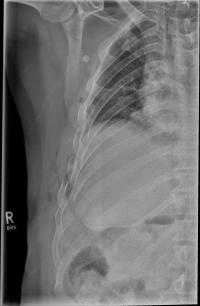

Rib Fractures

The rib fracture is a common injury to the chest. It occurs frequently in (car) accidents, falls during cycling and contact sports. Due to their anatomical position, especially the 4th - 9th ribs are affected.

As a rule, the rib fracture is diagnosed by X-ray. In severe cases or ambiguous X-ray findings, a layer imaging, for example computer tomography (CT), can also be performed.

In some cases, the sharp rib fragments cause lung or outer chest wall injuries. As a result, air can enter the gap between the lung and chest wall and cause a so-called pneumothorax, which must be treated by drainage.